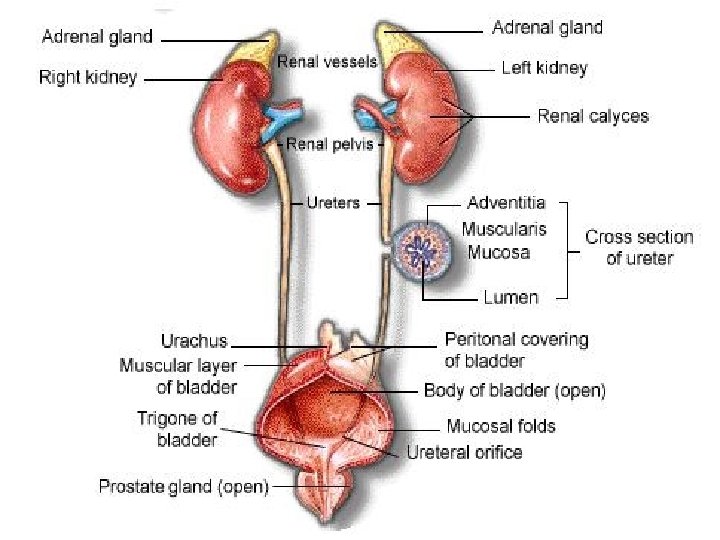

PARTS OF HUMAN EXCRETORY SYSTEM 1. Kidneys 2. Ureter 3. Urinary bladder 4. Urethra

KIDNEY • Kidneys are bean shaped organs that filtere 180 lt. blood in a day. • Blood is come into kidney by renal artery. • Filtered blood leaves from kidney by renal vein.

STRUCTURE OF KIDNEY 1. Cortex: It contains glomerulus and Bowman’s capsules. 2. Renal Capsule: It surrounds and protects the kidneys.

3. Medulla: It is located under the cortex and has malphigian pyramids. Malphigian pyramids contains urine collecting canal and loop of henle. 4. Pelvis: It is innermost part of kidney. The urine is collected in pelvis.